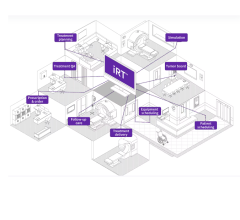

Sept. 25, 2025 — GE HealthCare has announced updates to Intelligent Radiation Therapy (iRT), a new version of the ...